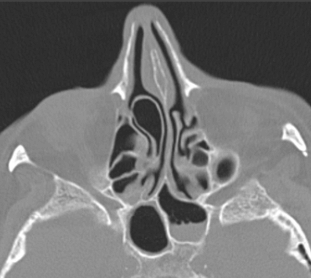

비중격만곡증의 경우 수술 전 다양한 검사를 하는데요 X-ray, CT, 후각통기도검사, 알레르기검사, 미각검사, 후각검사, 폐활량검사, 심전도검사, 혈액검사, 혈압검사등을 진행합니다 진행 후 전신수면마취가 아닌 국소마취를 통해 진행되며 수술시간은 30분 내외라고 합니다 개인의 코 상태에 따라 수술시간은 늘어나거나 줄어들 수 있으며 수술 후 코 점막의 상처가 아무는 시간은 2주 정도 소요됩니다 이 시기에 코안에 분비물이 생기거나 부울수 있으며 통증이 나타날 수 있는데요